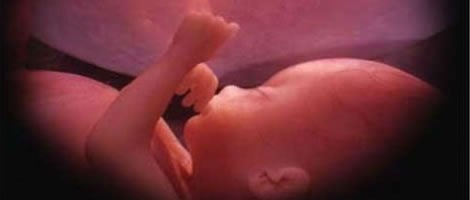

Neste mês o embrião passa a chamar-se de feto. No terceiro mês de gravidez todos os órgãos do bebé já estão desenvolvidos, apesar de ainda não estarem completamente formados. Precisam amadurecer e evoluir correctamente. Os genitais começam a definir-se mas ainda é cedo para determinar se o feto é um menino ou menina.

Ao longo destas três semanas o feto cresce mais de 7cm e pode chegar a pesar 20 gramas. A futura mãe engodará neste período cerca de 10% do total que engordará durante a gravidez.

Os movimentos do bebé nesta fase são bastante intensos e a futura mãe não deve alarmar-se com a sua intensificação. Esta mobilidade do bebé é um sinal de que está a evoluir correctamente.